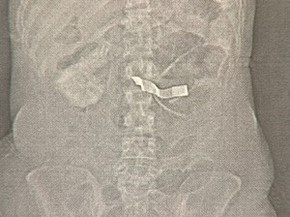

No último dia 17, ela deu entrada no Pronto Socorro de Taubaté e passou por exames. Uma fita branca foi localizada por meio do raio-x no estômago da paciente e ela foi encaminhada para São José, onde foi operada pelo médico Sebastião Batista Leite para a retirada da gaze - o mesmo médico acusado pela família de ter esquecido o material cirúrgico no estômago da jovem. A paciente morreu após a cirurgia. O profissional não faz parte do corpo clínico da Santa Casa..

Raio-x mostra imagem semelhante a gaze dentroda paciente. (Foto: Reprodução/TV Vanguarda)

O médico Sebastião Leite foi procurado, mas preferiu não dar entrevista. Especialistas foram consultados pela reportagem, mas por questões éticas preferiram não gravar entrevista. Eles disseram, com base na imagem do raio-x que o objeto é semelhante a uma gaze.